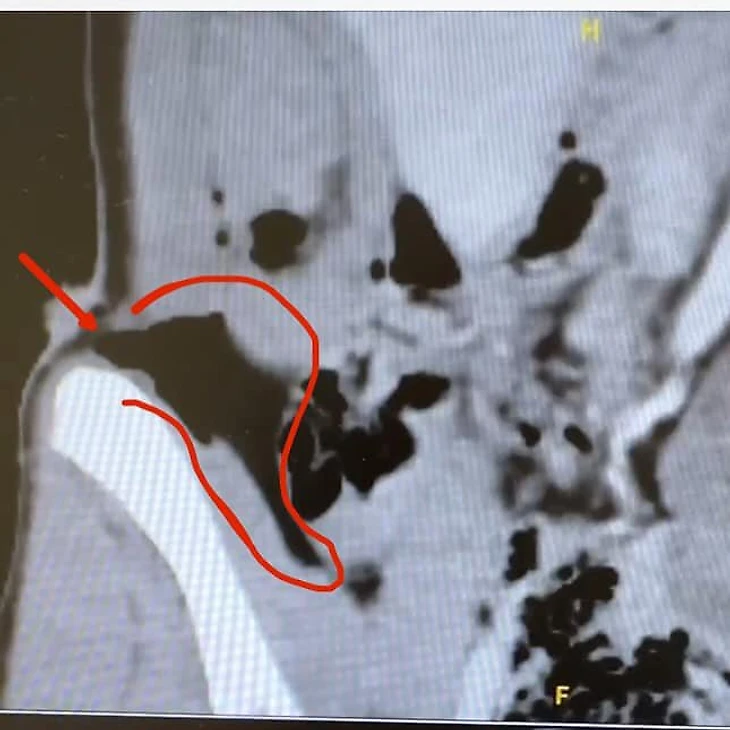

30 ноября 2024-го на этапе в Киллингтоне Микаэла лидировала после первой попытки в гигантском слаломе – до сотой победы оставалось немного. Но то ли они перестаралась, то ли звезды так сошлись, что вместо триумфа случился кошмар – Шиффрин упала и на высокой скорости влетела в ограждение, пропахав себе живот металлическим штырем.

Микаэла повредила мышцы живота, хотя, как сказали врачи, все могло быть куда хуже.

«Я рада, что не случилось худшего. Штырь прошел невероятно близко к органам. Если бы случилось так – ситуация была бы намного тяжелее», – рассказывала американка через неделю после падения.

Операции избежать все равно не удалось – Шиффрин позже делилась неприятными фото в соцсетях.